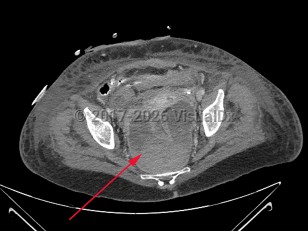

Perirectal abscess

A perirectal abscess is a collection of pus in the perianal area resulting from progression of an infected anal gland.

The diagnosis is made based on the history and a compatible physical examination. Imaging studies, including computed tomography imaging, may also be helpful.